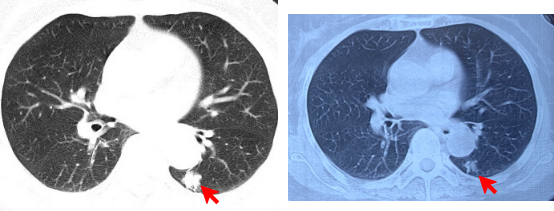

胸部CT显示抗真菌治疗后,左下肺结节病灶明显缩小。左图(2018-12-18),右图(2019-6-28)

经过口服抗曲霉菌的药物伏立康唑治疗,困扰陈阿婆十余年的咳嗽痰血消失了!半年后复查胸部CT,肺部小结节也渐缩小吸收。